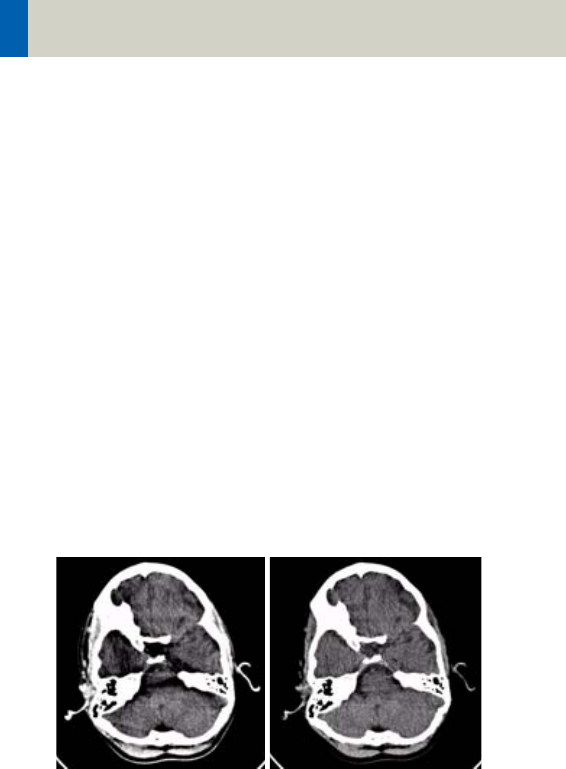

Head image without

correction.

Head image with

corrections.

Scan and Reconstruction